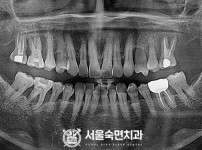

임플란트-전후사진1